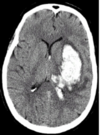

What view is this?

Axial